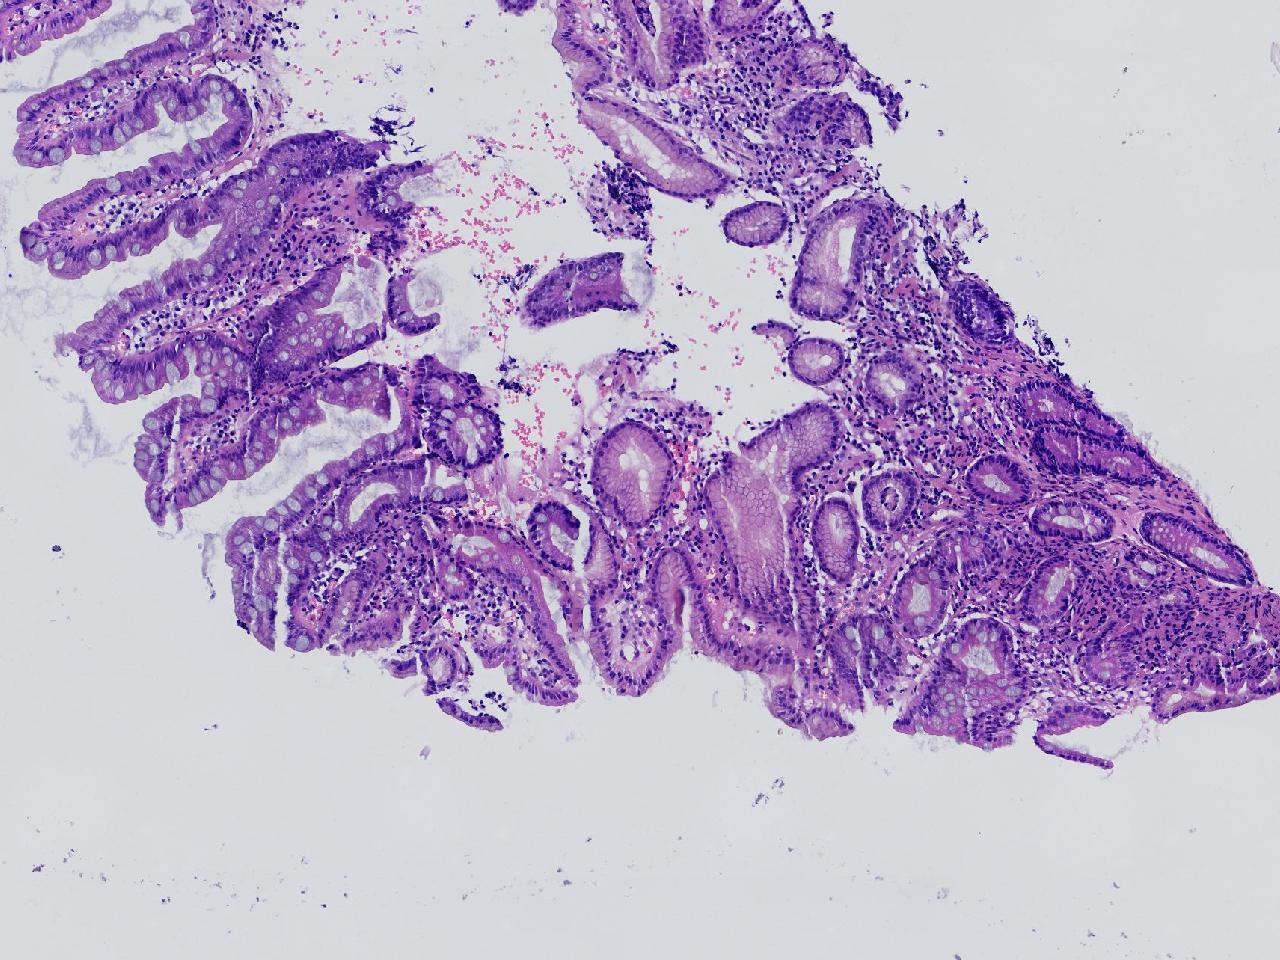

1.间质内淋巴组织有问题吗? 2.有没有低瘤变?

一般病史男,65岁,胃镜活检,胃窦粘膜红白相间,花斑样改变,大弯侧粘膜变薄,血管透见,可见多发片状充血糜烂灶及点状褐色物覆着,活检2块送检,质软弹性可。

标本名称胃窦活检

大体所见灰白色不整形软组织2块,直径均0.2厘米。

慢性萎缩性胃炎伴肠化,固有层淋巴细胞聚集

萎缩性炎,伴有肠化,淋巴组织挤压变形,感觉没有太大的问题。

炎性,无瘤变。